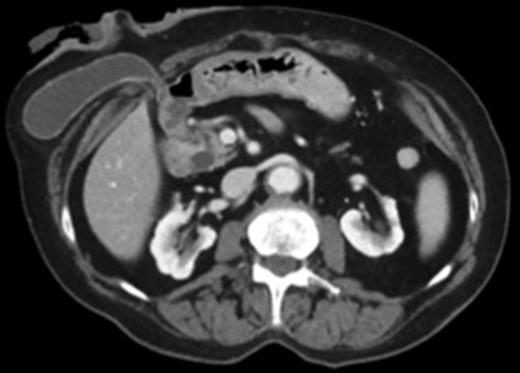

Subsequent Computed Tomography (CT) of the abdomen and pelvis revealed a parastomal hernia containing the gallbladder (Figs 1 and 2). There was no evidence of cholecysitis or choledocholithiasis. CBD was dilated to 9 mm without any filling defects.

Axial view CT scan of the gallbladder in the parastomal hernia.